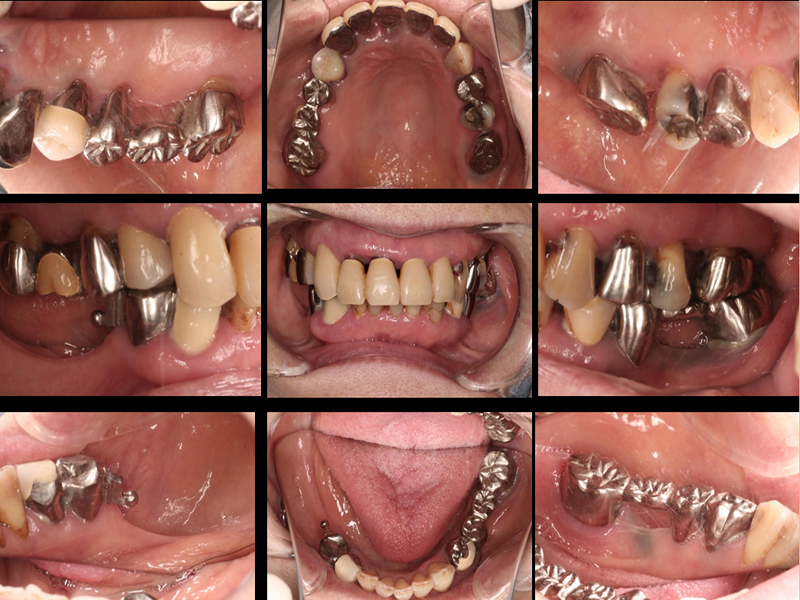

治療前の口腔内写真